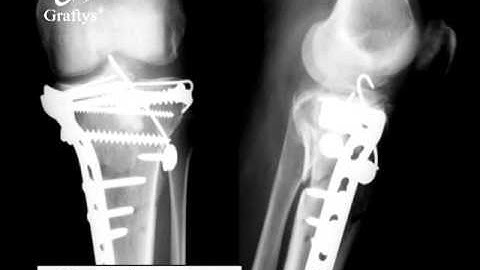

Tibia, Plateau - Bicondylar Fracture C3 - LCP 4.5/5.0 Proximal Tibia Plate & Bone Substitute